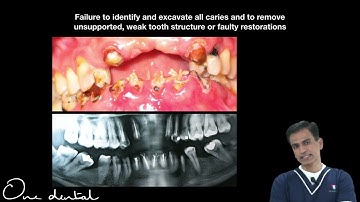

Endodontics II lecture 6. (Procedural Errors During Cleaning and Shaping)